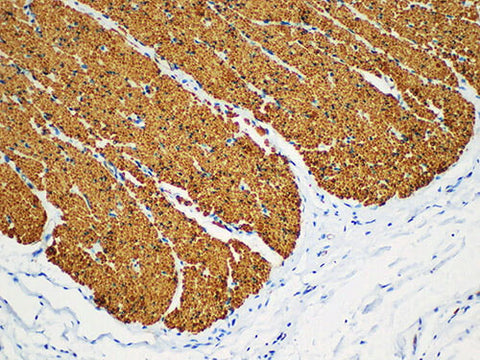

SMA Monoclonal Antibody Stored at -20°C

Applications IHC-P

Actin smooth muscle (SMA) is a kind of actin that marks smooth muscle. It can react with actin α isomer, but it has no cross reaction with actin skeletal muscle nor cardiac muscle. It is used to label smooth muscle and tumor of its origin. It can also be used to label myoepithelia and tumors of its origin. It can be used as an important reference for the judging of the above diseases to observe the distribution and existence of myoepithelium when judging the malignant lesions of mammary gland, sleeping fluid gland and sweat gland.